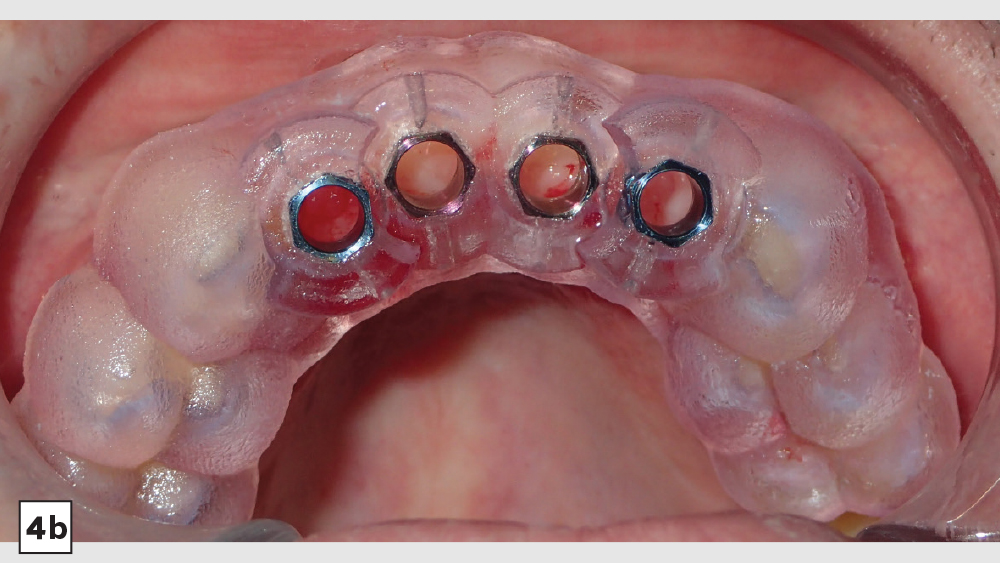

Digital treatment planning (DTP) with the team at Glidewell Laboratories allows me to ensure that implants are precisely placed, with full consideration given to the desired esthetics of the final restorations. But there was another unique element involved in planning the case described below: While it was esthetics that caused the patient to seek treatment, his career as a glass blower required his implants to be placed in functionally ideal positions. The potential complexity of these multiple requirements solidifed my decision to approach his case with implant positioning predetermined via DTP.

This patient came to me with four missing anterior teeth in positions #7–10. He had been missing these teeth for some time and was wearing a temporary denture to address the cosmetic issue this created. When he came to my practice, he was in a financial position to solve the problem permanently with implant restorations. Based upon the anterior space available and the fact that the patient’s surrounding tissue was in good health, I chose to move forward with Hahn™ Tapered Implants and BruxZir® Esthetic restorations.